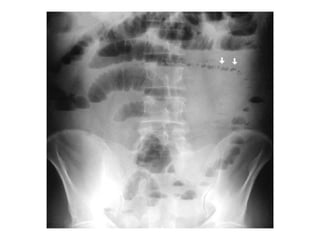

Este documento trata sobre la obstrucción intestinal, que ocurre cuando se detiene el movimiento del contenido a través del intestino. Describe las causas de la obstrucción, como cuerpos extraños, tumores, adherencias o volvulos. Explica la fisiopatología de la obstrucción, incluyendo la deshidratación, acidosis y choque. Finalmente, destaca los síntomas clave de dolor abdominal, distensión, náuseas y falta de emisiones, y los métodos de diagnóstico y tratamiento quirúrgico.